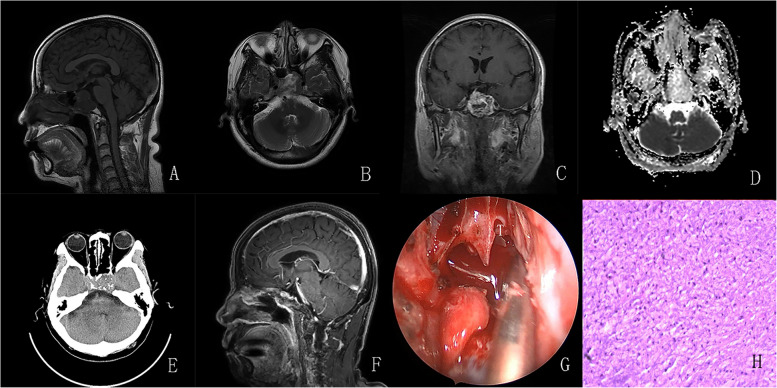

Conclusions: The preoperative diagnosis of sellar chondrosarcoma remains challenging and often requires differentiation from chordoma, INPA, or craniopharyngioma. When a calcified mass in the sellar region presents with intact or slightly disturbed anterior pituitary function, heterogeneous enhancement and no diffusion restriction on Magnetic Resonance Imaging(MRI) sequences, and surrounding bony destruction and bony attachment on Computed Tomography(CT) scans, a chondrosarcoma should be suspected preferentially. Complete resection is the optimal goal for the management of sellar chondrosarcoma, but adjuvant radiotherapy and periodic follow-up should be highlighted.